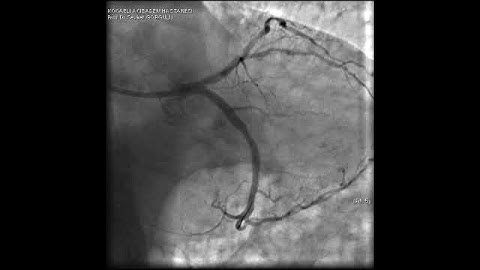

Tips & Tricks to wire a complex side branch ostial lesion!